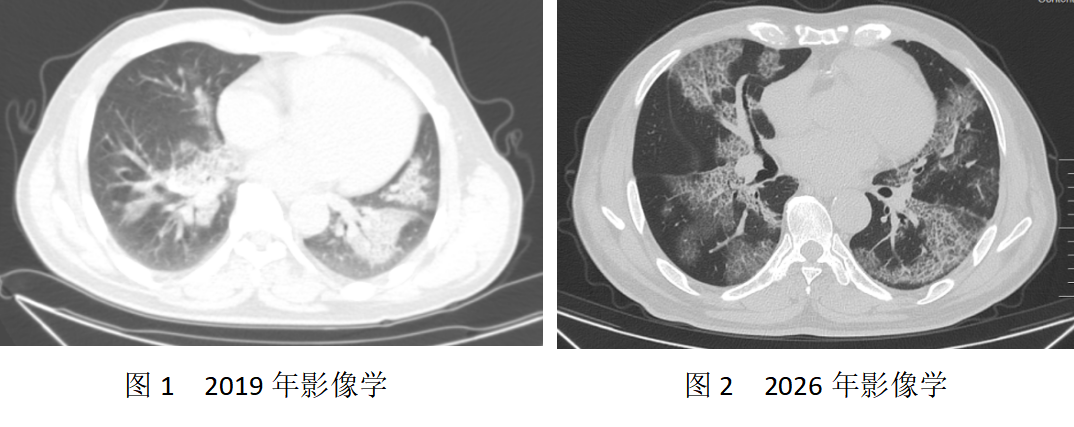

患者多年来受胸闷、喘息困扰,2019年首次就诊时,胸部CT显示双肺弥漫性密度增高,支气管镜下灌洗液呈浑浊石灰水样,虽被考虑为PAP,却未得到确诊和规律治疗,病情持续进展。2026年3月,患者因活动后喘息急剧加重、伴随咳嗽咳痰,辗转来到我院就诊,复查CT显示肺部病变较此前显著加重,呼吸功能严重减退,每一次呼吸都成为沉重负担。